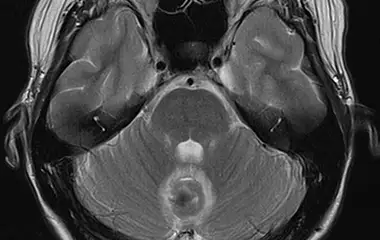

Kavernome

Kavernome sind in der Regel angeborene gutartige beerenartige Gefäßmissbildungen („Blutschwämmchen“), die zu Einblutungen (ca. 2-4 % pro Jahr) oder zu Epilepsie führen können und in diesen Fällen dann auch behandelt werden sollten. Sie können sowohl im Gehirn als auch im Rückenmark liegen. Sie haben keinen arteriellen Gefäßzufluss und führen daher (auf Grund des rein venösen und damit niedrigeren Blutdruckes, „low flow“) zu venösen „Sickerblutungen“ in das Kavernom selbst, die daher häufig kleiner ausfallen und die Patientinnen und Patienten weniger stark betroffen sind. Eine Ausnahme bieten Kavernome, die im Bereich des Hirnstamms liegen. Hier liegt die Blutungsrate bei bis zu 6% pro Jahr.

Durch Einblutungen progrediente und symptomatische Kavernome werden operativ therapiert. Embolisation und Bestrahlung spielen keine Rolle. Kavernome im Bereich des Hirnstamms stellen aufgrund der engen Lagebeziehung zu wichtigen anatomischen Strukturen eine besondere operative Herausforderung dar. Diese Hirnstamm-Kavernome stellen in unserer Klinik einen besonderen Behandlungsschwerpunkt dar.